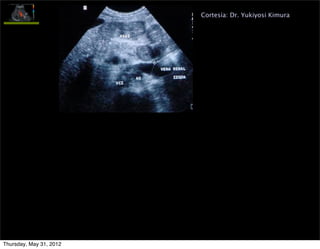

Cortesía: Dr. Yukiyosi Kimura

Signo de HP grave

(gradiente 15-28 mm

Hg)